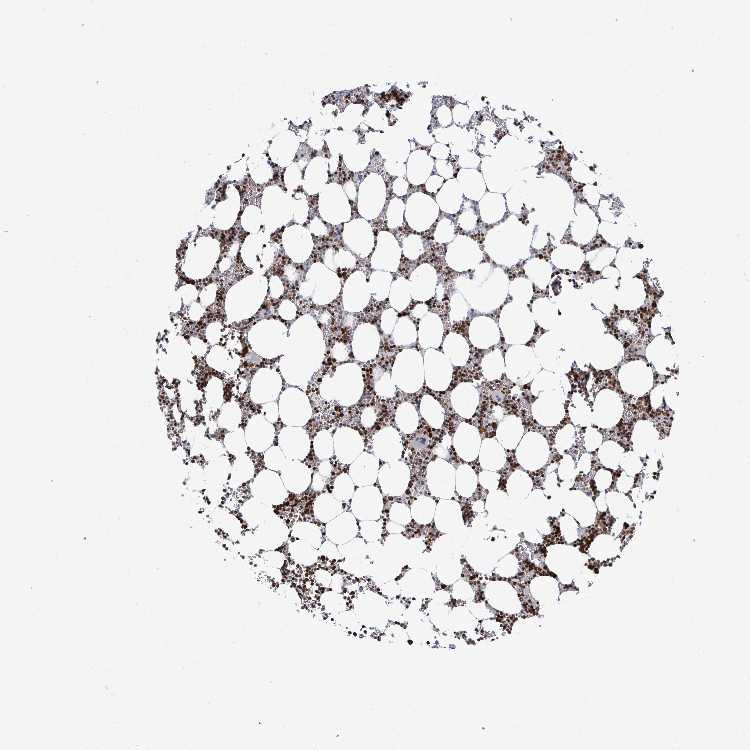

BONE MARROW - Antibody stainingi

Antibody staining in the annotated cell types in the current human tissue is reported as not detected, low, medium, or high, based on conventional immunohistochemistry profiling in selected tissues. This score is based on the combination of the staining intensity and fraction of stained cells.

Each image is clickable and will lead to virtual microscopy that enables deeper exploration of all samples and also displays staining intensity scores, fraction scores and subcellular localization as well as patient and tissue information for each sample.

Antibody HPA059098

Hematopoietic cells High